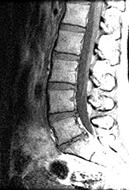

Some of the major causes of acute and chronic low back pain (LBP) are associated with radiculopathy. However, radiculopathy is not a cause of back pain; rather, nerve root impingement, disc herniation (see the image below), facet arthropathy, and other conditions are causes of back pain. [1, 2, 3]

Sagittal magnetic resonance image showing loss of intervertebral disc height at L5/S1. Herniations of the nucleus pulposus are noted at L4/5 and L5/S1. Courtesy of Barton Branstetter, MD